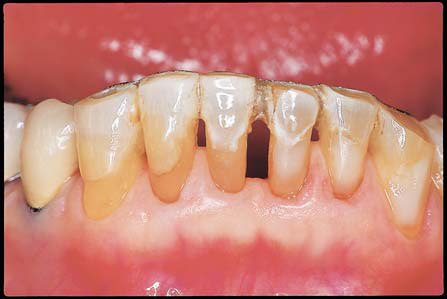

(図4)32年経過(2007年3月5日)、70歳。十分機能している

■症例:歯周疾患 (図1−6)

患者:71歳、女性。

著者が大学院学生時代からの長い付き合い(33年)の患者である。Sweetが大好物で、脂質異常症と高血圧症があるため、Sugar controlを常々指導するが、なかなか習慣は変えられないようである。長年、編み物教室の教師をしており、現在も毎日出張稽古で飛び回っているようである。ハイヒールをはいて社交ダンスを2〜3時間平気でしたり、毎年海外旅行へ行かれたり、非常に活動的な患者である。一時間かけて大阪から1回/月、定期的にSPTに努めてくれている。